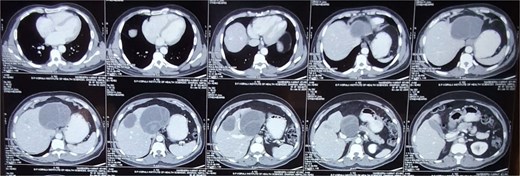

Following USG, a contrast-enhanced computed tomography (CECT) scan of the abdomen and pelvis was performed for further evaluation of the cystic lesions, including their size, location, wall thickness, and septations. The CECT scan revealed:

A well-defined, thick-walled (maximum thickness ~ 4.5 mm), multiloculated cystic lesion measuring ~8.9 × 9.7 × 9.4 cm (AP × TR × CC) with multiple thick enhancing septa (giving a honeycomb appearance) involving segments II and III of the left lobe. Laterally, it was abutting the left portal vein and inferiorly abutting the main portal vein.

Another well-defined, thick-walled (maximum thickness ~6.5 mm) cystic lesion measuring ~5.6 × 4.4 × 4 cm (AP × TR × CC) with enhancing septa located in segment V of the right lobe.

Based on the clinical presentation and imaging findings, the patient was diagnosed with Stage CE 2 WHO-IWGE classification hepatic hydatid cyst with bilobar involvement.

For diagnosing hepatic hydatid disease, imaging studies play a crucial role. Computed tomography (CT) is the investigation of choice (as shown in Fig. 1), with a specificity of 98%, while USG has a sensitivity of 90%–95% [1]. Both modalities are highly accurate in diagnosing hepatic hydatidosis, allowing for the assessment of cyst structure, number, location, and potential complications.